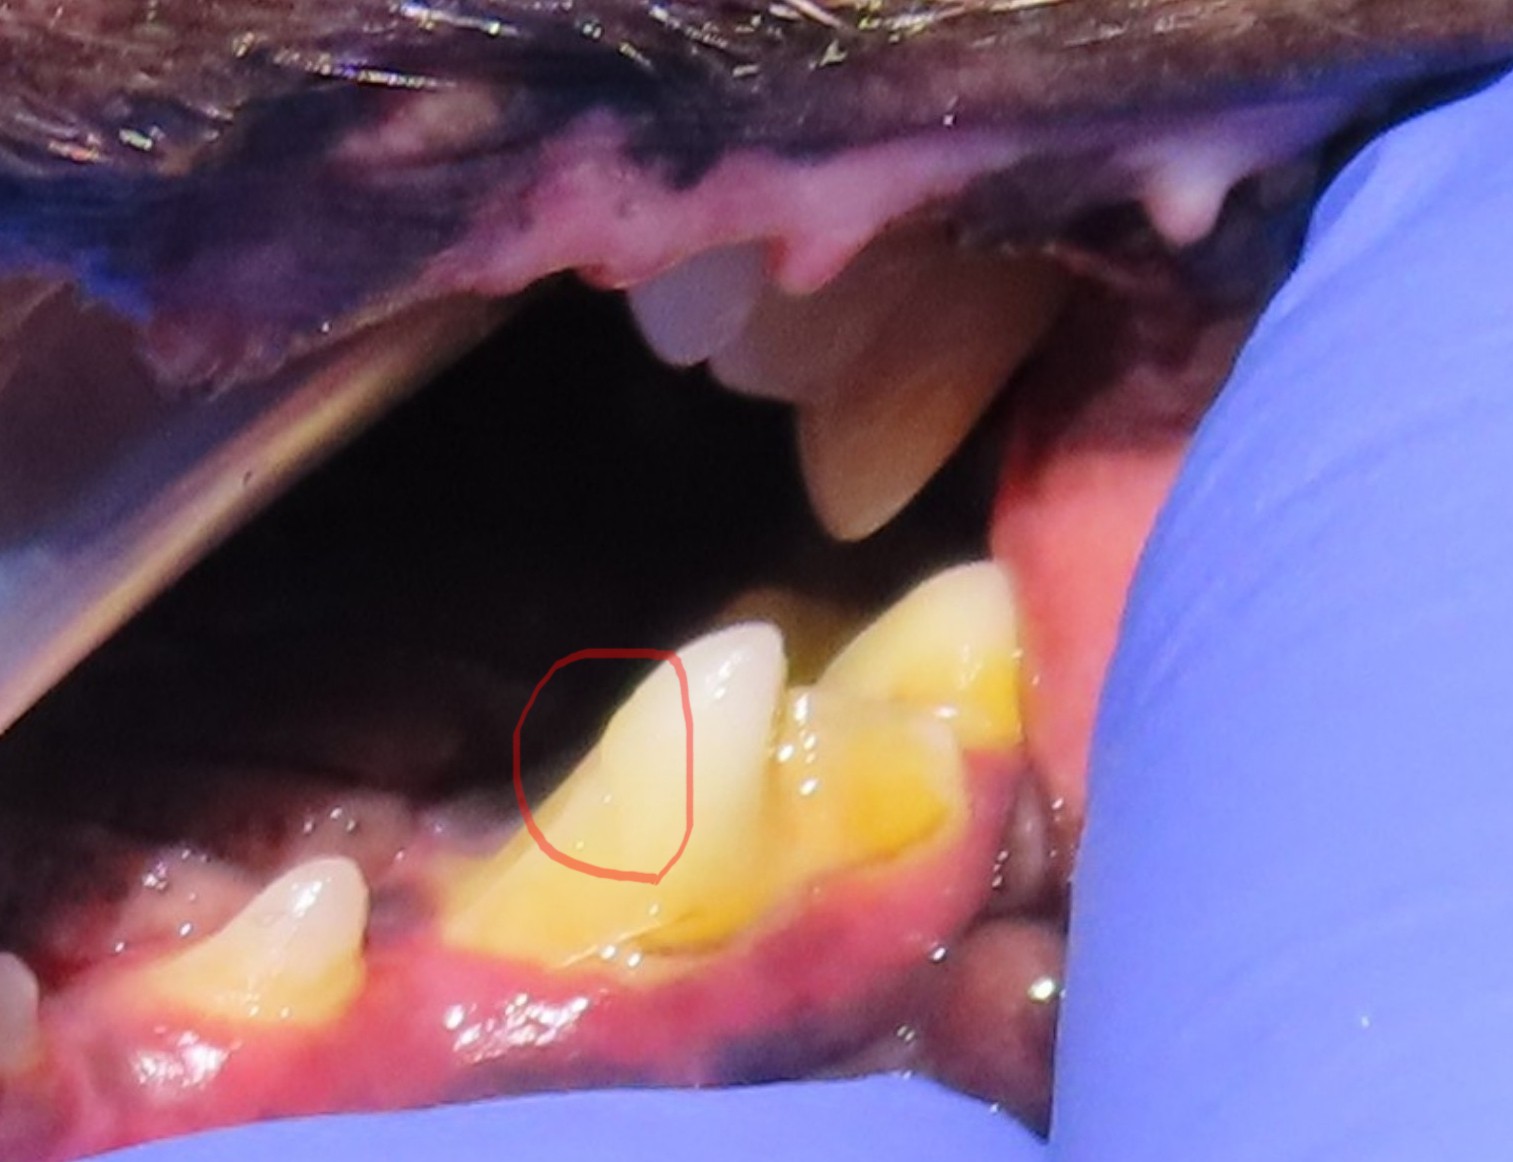

이번 사례 역시 처음엔 치석이 두껍게 붙어 있는 단순한 구강 문제처럼 보였지만, 확대해서 살펴보니 치아 표면이 불규칙하고 금이 간 선이 명확히 보였던 경우였습니다.

외형상 단순하게 치석이 긴 치아처럼 보였지만, 확대 관찰을 해보니 표면이 매끄럽지 않고 치아 표면에 미세한 금이 간 것이 확인되었습니다. 이 부위는 단순한 착색이 아니라 법랑질과 상아질이 분리된 균열선, 즉 치아가 실제로 끊긴 치관 파절이었습니다.